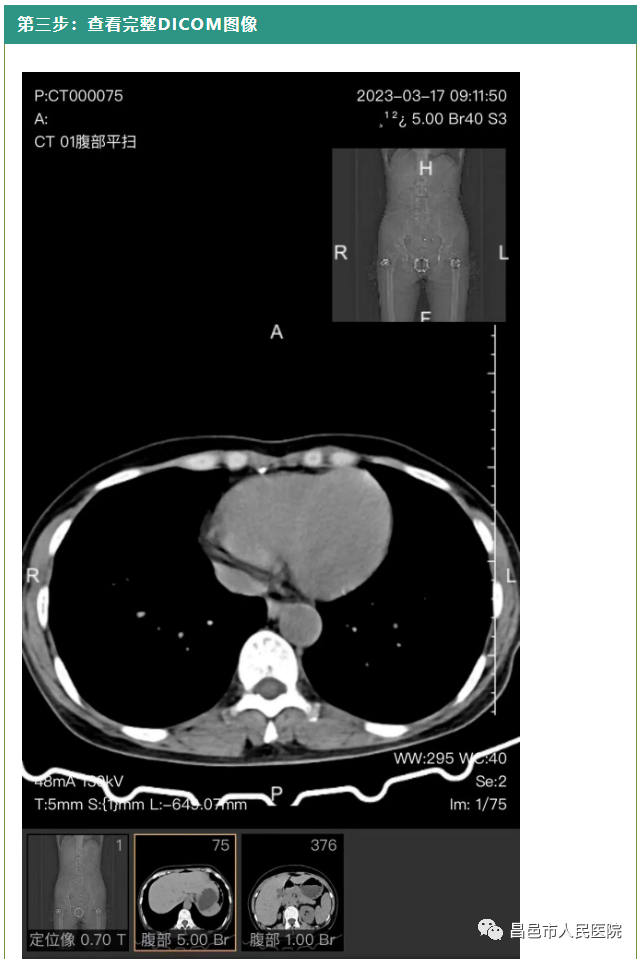

电子胶片使图像信息更完整、更连续,传统胶片只包含部分压缩图像,且无法进行参数调节、放大等动态显示;需要到外院就诊时,医生很可能要求患者重新做检查,不仅不方便,费用支出也会相应增加;云胶片突破了传统物理胶片对于图像帧数的限制,能够为患者提供此次检查的全部 DICOM 原始影像,并具备缩放、移动、窗宽调节等多种图片处理功能,高清晰的原始图像方便患者查看,也更利于医生对病灶进行细节分析,提高诊断效率和精准度。